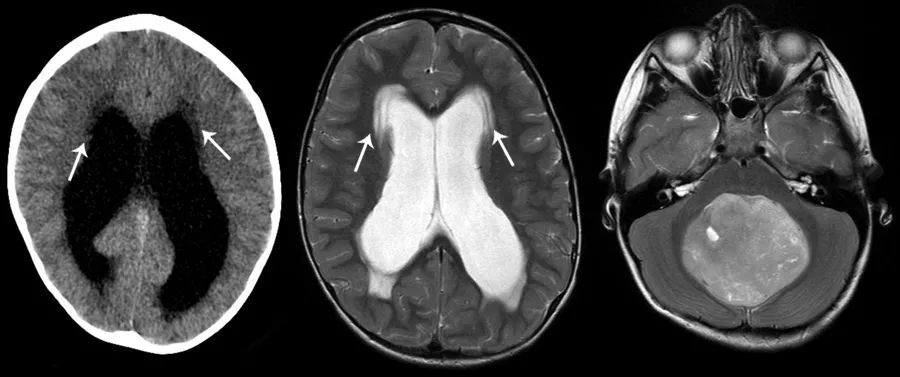

图5 侧脑室周围可见条片状异常密度,CT上呈低密度,MRI的T2WI上呈高信号,边界较清(左、中)。本例患者的阻塞性脑积水由后颅窝占位导致(右)。